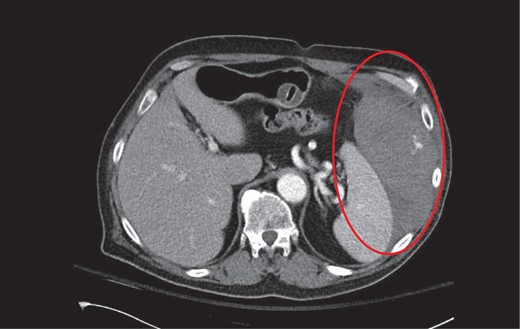

CT coronal with intravenous contrast demonstrating intraperitoneal blood products within the perisplenic region and left paracolic gutter.